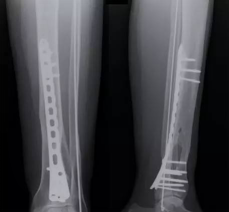

内固定

接骨板、螺钉

C:\Users\ADMINI~1\AppData\Local\Temp\ksohtml5168\wps19.png

髓内钉、克氏针

C:\Users\ADMINI~1\AppData\Local\Temp\ksohtml5168\wps20.pngC:\Users\ADMINI~1\AppData\Local\Temp\ksohtml5168\wps21.png